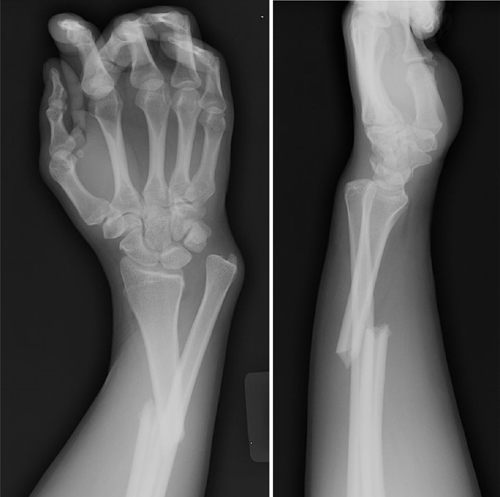

Describe the abnormality demonstrated.

Comminuted fracture of the distal radius and widening of the distal radio-ulnar joint (Galeazzi)